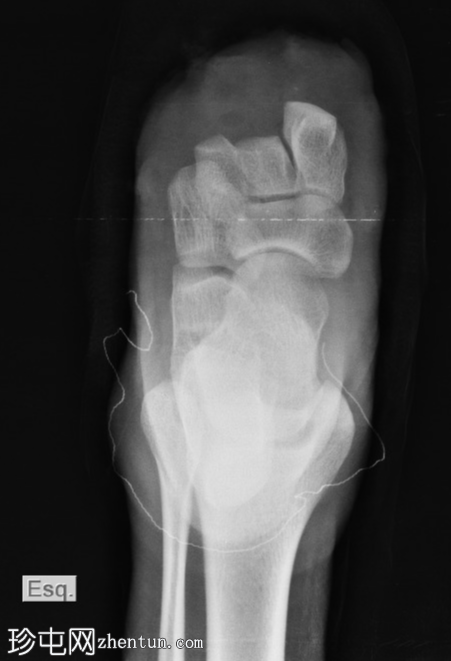

X线片

正位

第一跖趾关节脱位。

第二跖骨头粉碎性骨折脱位。

第三跖骨骨折伴节段性骨缺损。

第五跖骨颈移位性骨折。